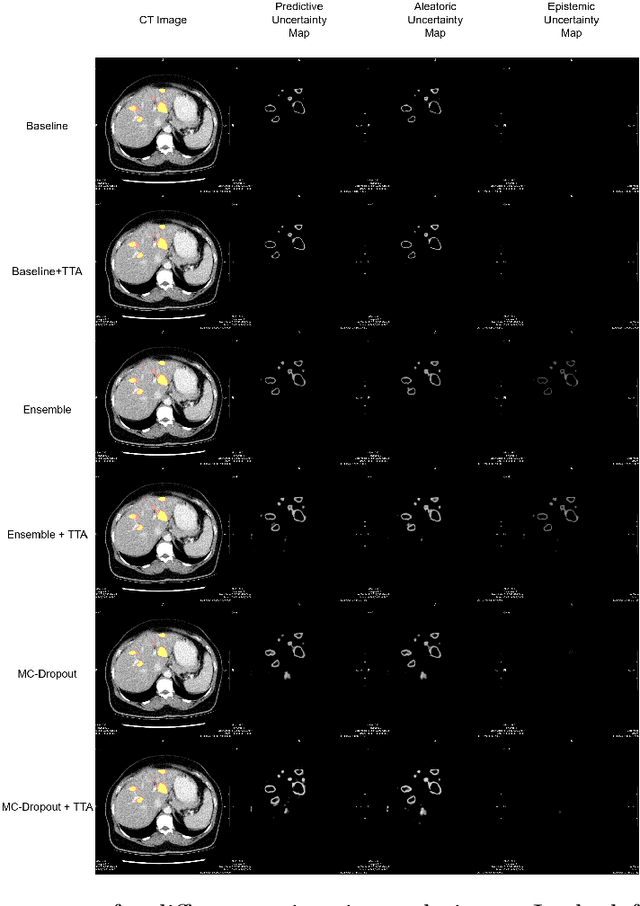

Deep learning techniques show success in detecting objects in medical images, but still suffer from false-positive predictions that may hinder accurate diagnosis. The estimated uncertainty of the neural network output has been used to flag incorrect predictions. We study the role played by features computed from neural network uncertainty estimates and shape-based features computed from binary predictions in reducing false positives in liver lesion detection by developing a classification-based post-processing step for different uncertainty estimation methods. We demonstrate an improvement in the lesion detection performance of the neural network (with respect to F1-score) for all uncertainty estimation methods on two datasets, comprising abdominal MR and CT images respectively. We show that features computed from neural network uncertainty estimates tend not to contribute much toward reducing false positives. Our results show that factors like class imbalance (true over false positive ratio) and shape-based features extracted from uncertainty maps play an important role in distinguishing false positive from true positive predictions